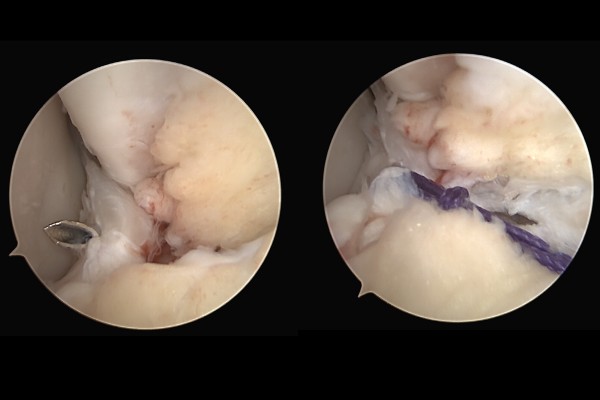

내시경 사진을 보시면 인대가 파열되어 끊어져서 뼈(바깥쪽 복숭아뼈, 비골)에 붙어있지 못 하고 틈이 보이는 것이 확인됩니다.

파열된 인대를 바늘과 같은 수술도구로 떠서 실을 통과시켜 묶어 줍니다.(실은 칼슘나사와 결합되어 있습니다.)